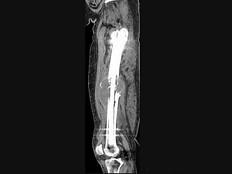

问题 男,18岁,右股骨肿瘤术后,现大腿中部疼痛、肿胀,夜间尤甚,结合CT图像,最可能的诊断是 ( )

选项 A、成骨性骨转移瘤 B、化脓性骨髓炎 C、Ewing肉瘤 D、骨肉瘤 E、骨纤维肉瘤

答案 D